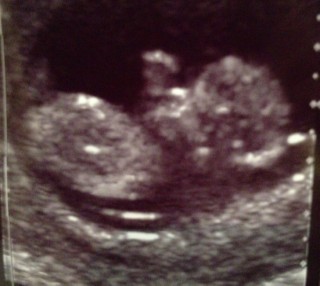

妊娠12目の時のエコーです。 とても元気で驚きました。まるで魚が川の上を飛び跳ねるように激しく動いていて、こんなに小さいのに強いエネルギーを感じました。 かと思えば、疲れてしまったのか、まったく動かずじーっとしたり。とにかく初めてのエコーだったのでとても感動しました。

元気良く動いていました!

はっきりと手足が確認出来たので安心しました。

頭からおしりまで約6cm♪ 寝てると思ったら起きたのか手足をバタバタさせて元気な姿が見られて安心しました(*^^*) 指が可愛いくて癒されてます♪

ちゃんと人間の形になっててビックリ!

背骨が見えます。前回(9w)の時はよく見えなかったけど、人間らしくなり、より実感がわいてきました。